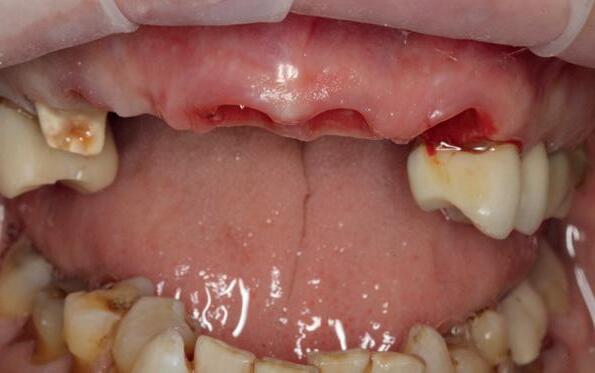

Op maandagochtend halfnegen dient zich in mijn agenda een nieuwe patiënt aan, mevrouw G. Ik heb haar nooit eerder gezien en een verwijzend tandarts, stuurt haar in met de vraag of ik met implantaten het eerste kwadrant wil restaureren aangezien daar de brug is losgekomen. Eerder heeft mevrouw G. een uitgebreide informed consent ontvangen met een gezondheidsvragenlijst. Er is verder intensief contact geweest met de verwijzer die ook enkele gemaakte röntgenfoto’s heeft gemaild. Tijdens het eerste onderzoek blijkt dat ze zich goed heeft ingelezen in alle informatie die haar per mail is toegestuurd. De patiënt is 65 jaar oud, spreekt moeilijk Nederlands, echter in het Engels kan ze zich goed verstaanbaar maken. Bij navraag blijkt ze in verschillende landen te hebben gewoond in verband met de werkzaamheden van haar man. Ze is van een economisch hogere sociale klasse en woont nu sinds een jaar of vijf in Nederland. Ze is gezond en slikt geen medicijnen, behalve pijnstillers tegen de pijn in haar gebit.

Er worden lichtfoto’s gemaakt van het gebit waarop blijkt dat enkel een aantal incisieven in boven- en onderkaak onbehandeld zijn (zie lichtfoto’s bij intake). De residentie lijkt vrijwel geheel gekroond en/ of overbrugd. Er is sprake van gedateerd kroon- en brugwerk waarbij kroonranden met de jaren bloot zijn komen te liggen en er is sprake van secondaire cariës. Daarnaast stel ik een fors verlies van verticale hoogte van de aanwezige processus in alle vier de kwadranten vast. Is hier sprake geweest van een verleden met ernstige parodontitis?

Op basis van de eerste indruk die ik krijg tijdens het globale klinische onderzoek, wordt een orthopantamogram (zie OPT bij intake) gemaakt. Samen met de meegestuurde röntgenopnames (zie solo’s) wordt eenvoudig vastgesteld dat er sprake is van ernstig botverlies, bijvoorbeeld bij de 16, 17 en de 18 tot 100% verlies aan alveolair bot. De 16 vertoont daarnaast een grote peri-apicale laesie. In het eerste kwadrant lijkt daarom alleen de 12 een goede prognose te hebben. De 12 vormt samen met de 16 een vierdelige brug en deze constructie lijkt dus verloren. Overigens vermoed ik dat de 12 eigenlijk een cuspidaat is en ontbreekt de 12 (agenesie). Daarnaast worden sterk verdiepte ontstoken pockets geconstateerd bij de 16, 17 tot 12 mm en zijn de elementen sterk verhoogd mobiel. De 11 lijkt als enige element van de gehele dentitie niet te zijn behandeld.

Dit betekent in eerste instantie dat de dentitie invasief wordt gesaneerd wat neerkomt op totaal extractie: een volledige gebitsprothese voor in de boven- en onderkaak. Een implantaat gedragen vaste voorziening kan op termijn aan de wens van de patiënt voldoen. De chirurgische behandeling omhelst het plaatsen van implantaten op geleide van een boormal eventueel in combinatie dan wel separaat uit te voeren botopbouw en bilaterale sinuslift. Zes maanden na de eerste fase wordt het mogelijk de tweede fase uit te voeren, namelijk de abutment chirurgie. De immediaat gebitsprothese dient als (tijdelijke) noodvoorziening en wordt tussentijds aangepast.